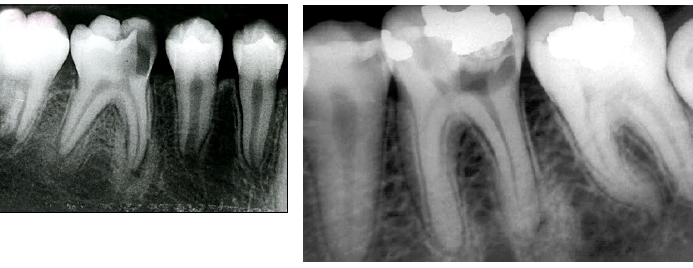

contrast with condensing osteitis

if the tooth is non vital - condensing osteosis

condensing osteitis

features of condensing osteitis

non-vital tooth or presence a source of inflammation

widened PDL

sclerosis of bone around roots in response to chronic inflammation

may mimic idiopathic osteoscerosis